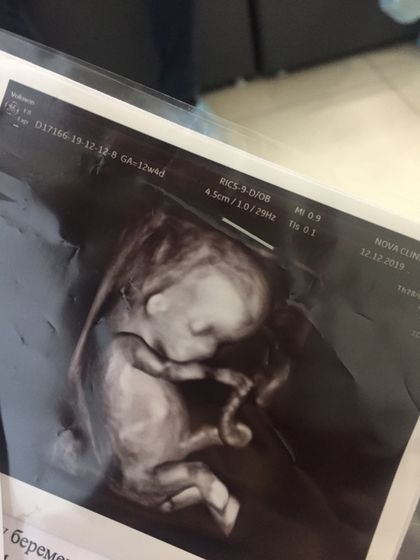

Прошли скрининг! Я так долго ждала этот день ? Для нас он был в разы волнительней, ведь я пережила и лапараскопию на 4й неделе, и кучу нервов… поэтому очень боялась чтобы не было последствий. На УЗИ всё чики-пики, пальчики считали, косточки измеряли, ребёнок там прям кувыркался, ЧСС в норме, врач такая «сюси пуси какой хорошенький» ?а я лежу в шоке и не верю что во мне уже такое ДИТЯ. Улыбка не сходит. Уже всем бабушкам, дедушкам, сёстрам, братьям — всем скинула фотоотчет ? Конечно лучше было после результата анализа крови, но я ждать не могуууу, я слушала все ок, значит ок))

Поздравляю!))У вас 3д узи?

Спасибо!))Сам осмотр органов, все замеры всё было обычным узи, а в конце она сделала фоточку 3д ?